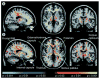

Figure 1. Diffusion tensor functional anisotropy group statistical maps

(A) Pre-Huntington’s disease. (B) Huntington’s disease. Exploratory whole-brain analyses demonstrated significant reductions in functional anisotropy in the internal capsule, frontal subcortical WM and portions of the thalamus, and increases in functional anisotropy in the putamen in the group of presymptomatic individuals known to carry the genetic mutation that causes Huntington’s disease (pre-Huntington’s disease), paralleling the results of the region of interest analysis. In the early-stage Huntington’s disease group, significant increases in the putamen and globus pallidus were observed; reductions in functional anisotropy included the internal capsule, corpus callosum, external/extreme capsule, cerebral peduncles, brainstem and WM underlying brain regions, including sensorimotor cortex, frontal, parietal and parieto–occipital areas. Blue areas show areas of statistically significant increases in functional anisotropy; yellow areas show areas of statistically significant reductions in functional anisotropy. WM: White matter. Reproduced with permission from [33];.